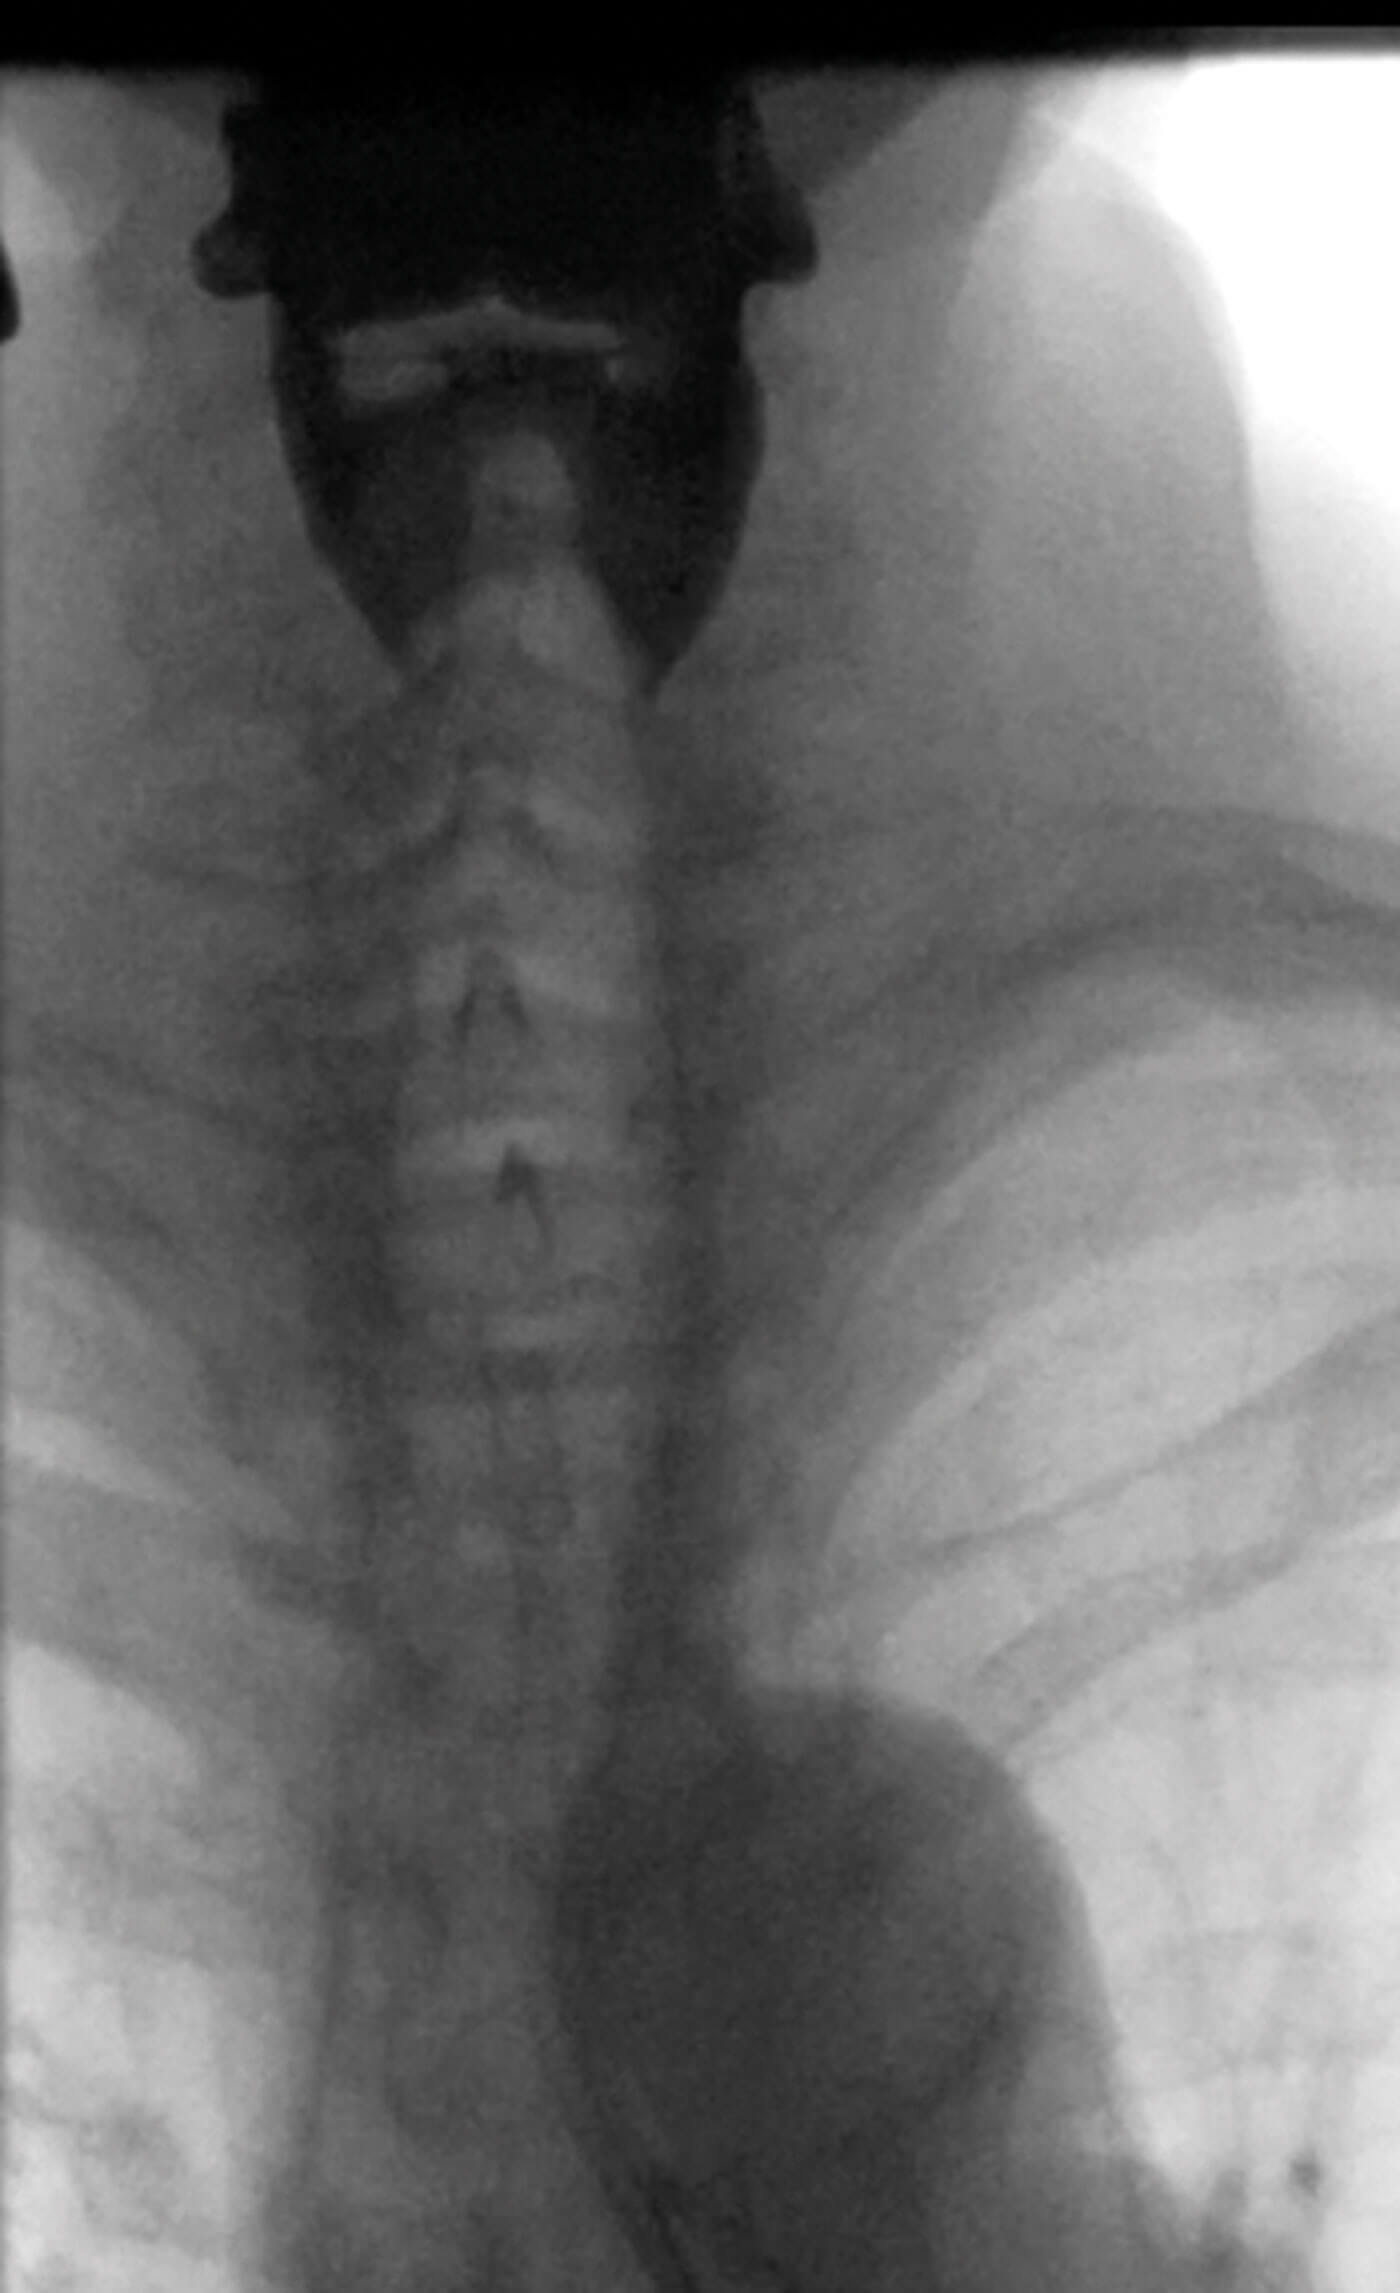

Fluoroscopic image of bilateral high pharyngeal diverticuli (white diverticuli)

that typically drain spontaneously and are asymptomatic.